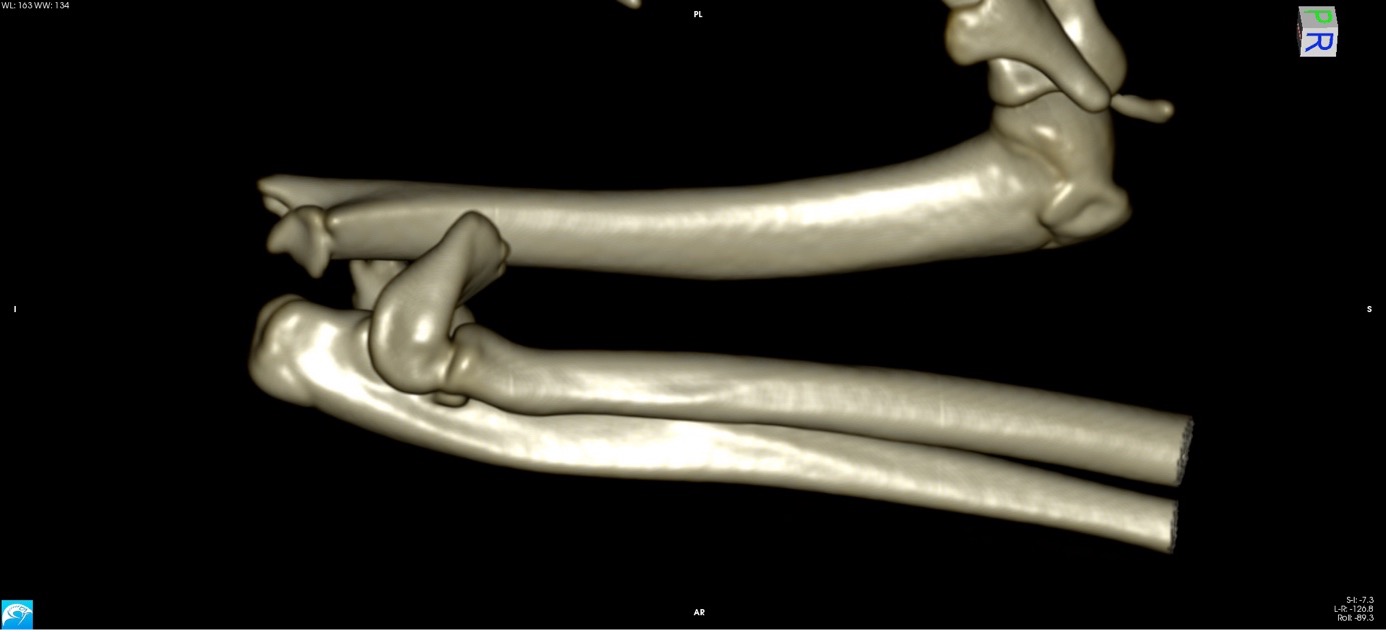

Exemple 2 :

Figure 4 : Pré-Op